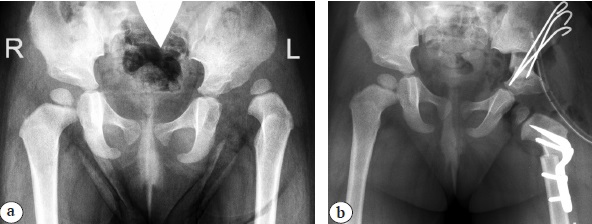

In group II, after identical manipulations both inside the joint and on the femur and a similar exposure of the ilium, an angular pericapsular section of the inner and outer cortical layers of the ilium was performed with chisels so that the vertical part of the section passed at a distance of at least 0.5 cm from the posterior column of the pelvis and strictly parallel to it. Subsequently, using spreaders, the acetabular hood was “folded” outward and anteriorly, whereas the posterior pelvic column remained intact (Fig. 3).

Fig. 3. X-rays of hip joints in an anterior-posterior projection of patient born in 2018 with hip dysplasia IHDI type III: a — before surgery; b — after surgical treatment using the Pemberton pelvic osteotomy